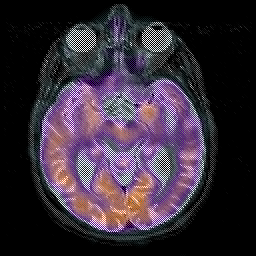

Alzheimer's disease, overlay -- Slice #20

[Home][Help][Clinical][Tour 1][Tour 2] Slice 20